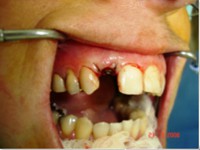

Carga Imediata após exodontia atraumática

Fatos interessantes pertinentes a este caso:

- Extração imediata

- Implante imediato

- Carga imediata

- Coroa protética cerâmica imediata